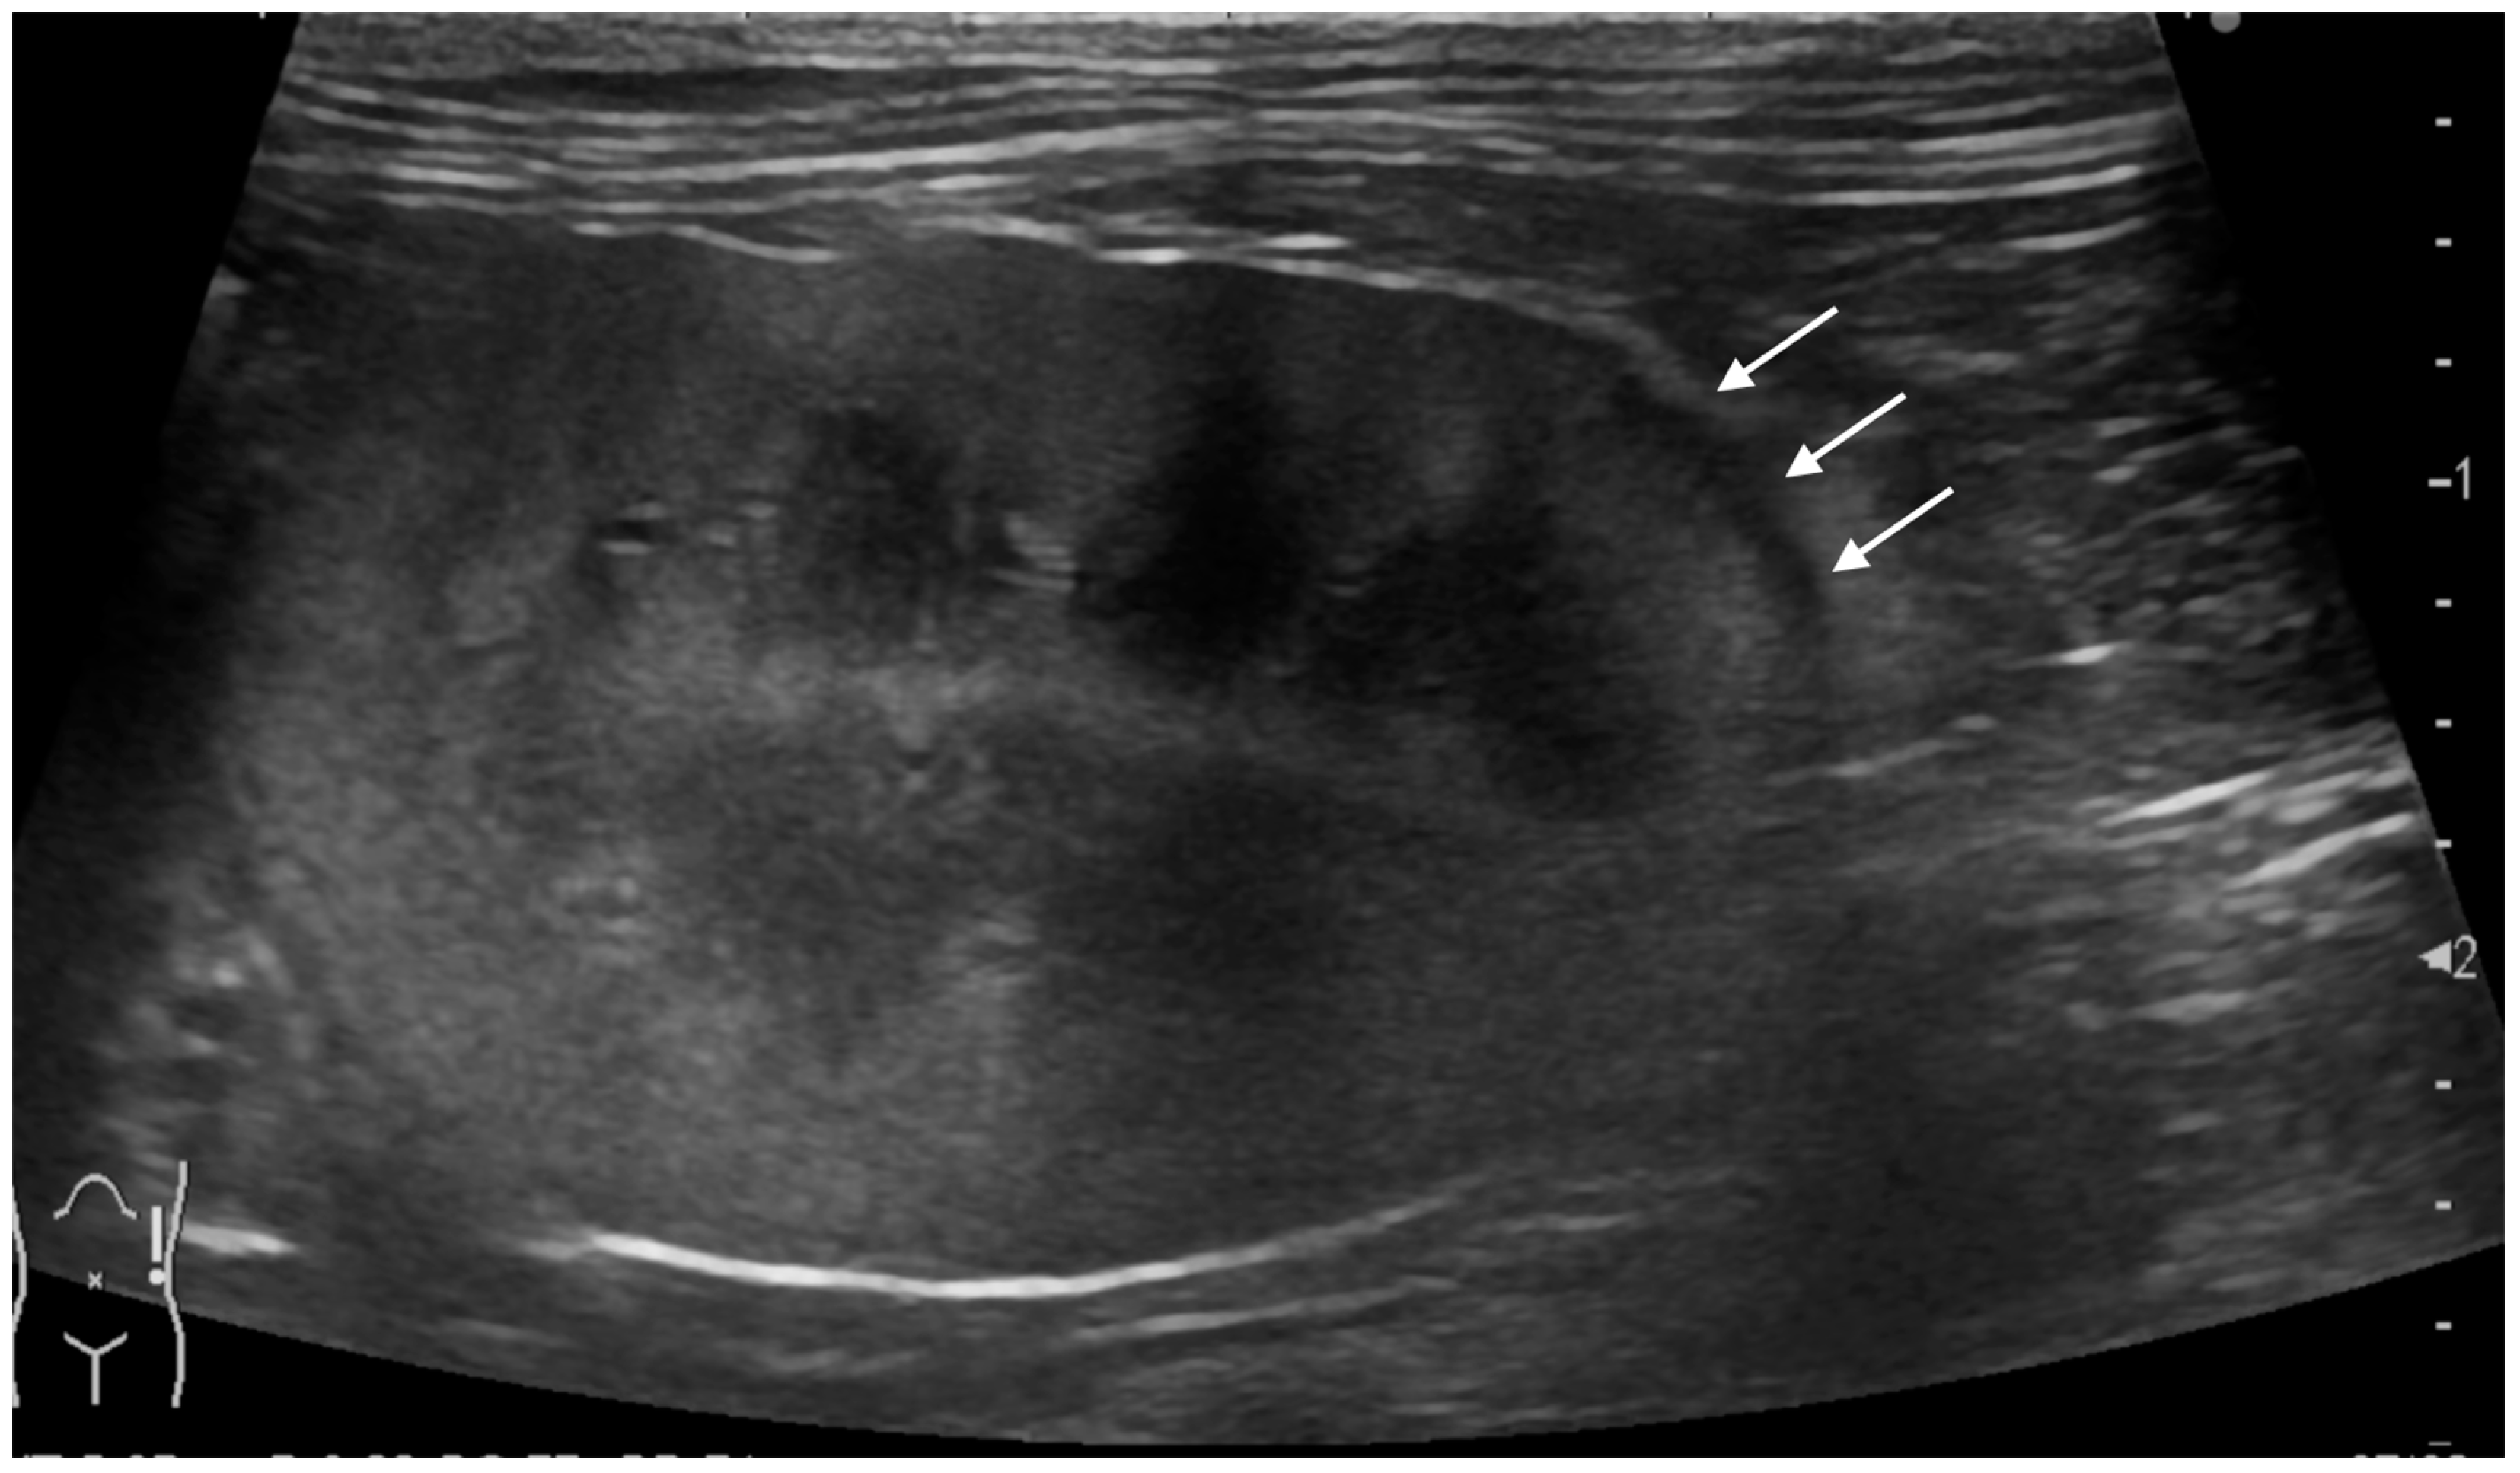

In our study population, renal subcapsular thickening was observed bilaterally in three cats, unilaterally in the left kidney in two cats, and in the right kidney in one cat, for a total of nine kidneys from six cats. For the image evaluation, 1–15 images and 0–2 videos were available per kidney. The ultrasonographic findings and diagnoses are listed in Table 1. The ultrasonographic evaluation showed that the maximum thickness of the subcapsular thickening ranged from 1.0 to 13.2 mm (median 3.0 mm), with one kidney with primary renal carcinoma showing a markedly thickened lesion (13.2 mm), while the others (metastatic carcinoma) were less than 5 mm in thickness. The distribution of the subcapsular thickening lesion was focal in eight kidneys (8/9; Figure 1, all metastatic carcinomas) and circumferential in a single kidney (1/9; Figure 2, primary renal carcinoma). In all eight metastatic carcinomas, the kidney showed focal, homogeneous, and hypoechoic subcapsular thickening (Figure 1). In a primary renal carcinoma kidney with circumferential thickening, the subcapsular thickening was heterogeneously mixed isoechoic to hypoechoic relative to the renal cortex (Figure 2).

The renal cortical margin was smooth in five kidneys (5/9; Figure 3) and irregular in four kidneys (4/9; Figure 1, Figure 2 and Figure 4). The capsular margin was smooth in five kidneys (5/9; Figure 3) and irregular in four kidneys (4/9; Figure 1, Figure 2 and Figure 4). Blood flow was assessed in five kidneys using color Doppler. The vascularity was observed within the thickened subcapsular lesion in two kidneys (2/5). Perirenal effusion was only observed in one cat, bilaterally.

Figure 1. Ultrasonographic image of a kidney with metastatic pulmonary carcinoma (case 1, left kidney). A thin, homogeneously hypoechoic subcapsular thickening (*) was present focally along the ventral aspect of the kidney (a). There was no vascular flow observed within the subcapsular thickening using color Doppler (b).